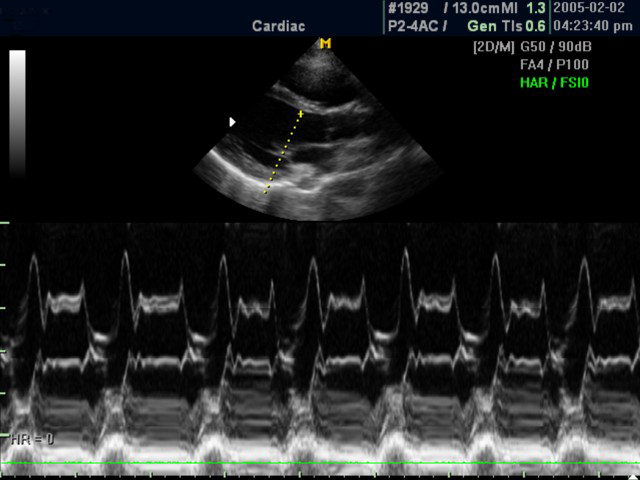

Анатомический M-режим (Free-angle M-mode) - это возможность вращения курсора в М-режиме под произвольным углом (при фиксированном положении датчика) и, соответственно, получения графика движения структур сердца в различных произвольных плоскостях.